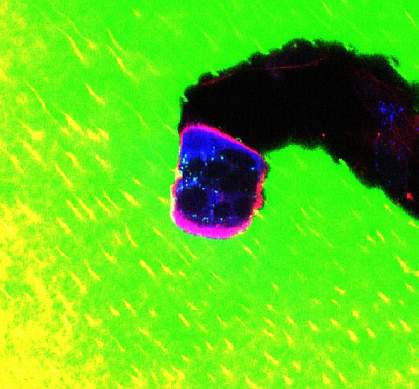

In the online edition of Nature on February 8, 2009, the researchers reported that osteoclasts express S1P receptors on their surface. They also migrate toward S1P in the laboratory. The researchers next used an imaging technique called 2-photon excitation microscopy to image bone tissue in a live mouse. Adding drugs into blood that activate the S1P receptor, they found, caused immature osteoclasts to migrate away from bone.